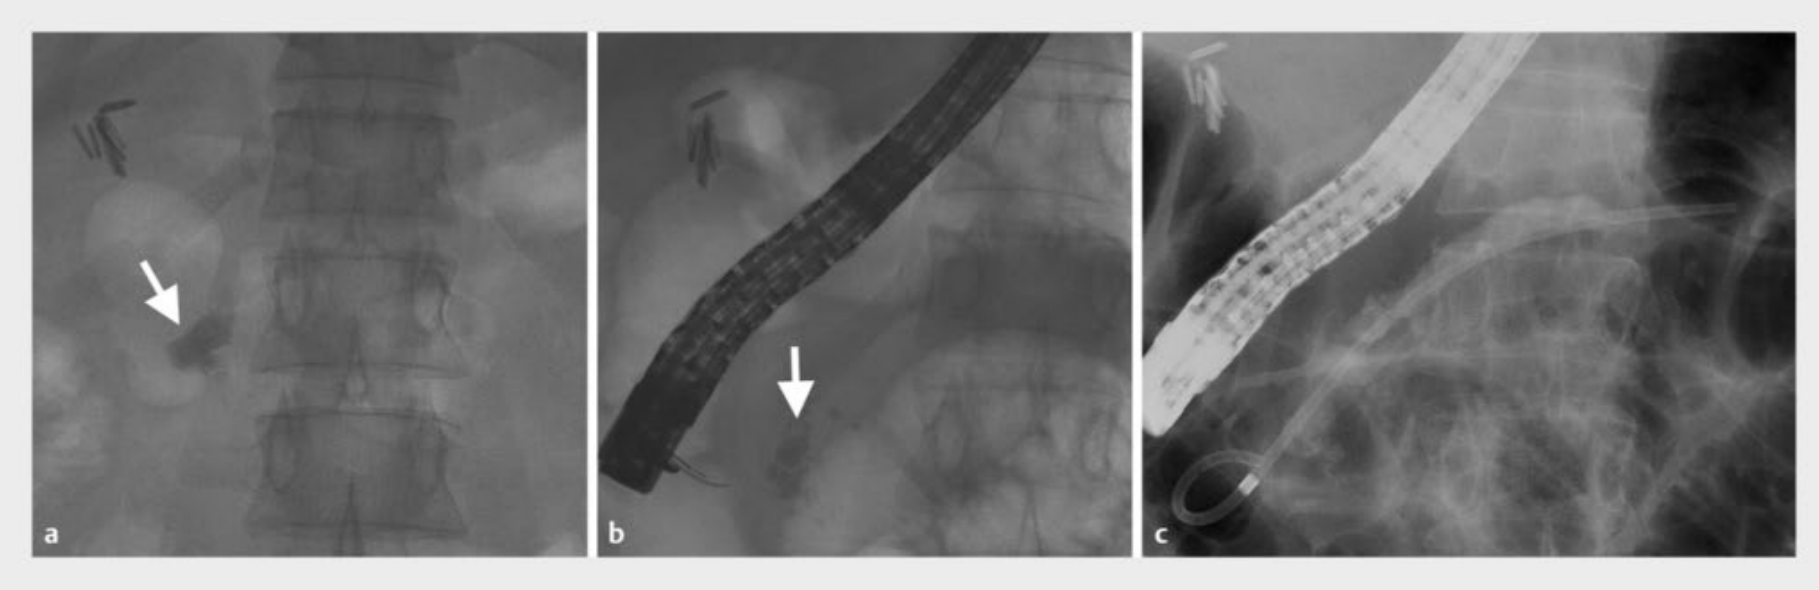

ESWL是用第三代电磁碎石机进行的,具有透视和超声成像设施。不透射线的结石(图1 a)在透视引导下直接定位,而放射透明结石在碎石术中借助鼻胰管引导下对比剂注射定位。每次治疗进行5000至6000次电击,强度为15-16kV,频率为每分钟90次电击。每天电击,直到碎成<3毫米或MPD中结石的异质性降低。如果四次ESWL后没有碎裂,则定义未手术失败,建议患者手术。ESWL在硬膜外麻醉下进行。MPD清除定义为完全(清除>90%的结石体积)、部分清除(50%-90%的结石体积)和不成功(碎裂或清除<50%的结石体积)。

图1. 透视图像。a头部区域不透射线结石(箭头)。b胰腺碎石后碎裂结石(箭头)。c内镜逆行胰腺造影并置入胰管支架。